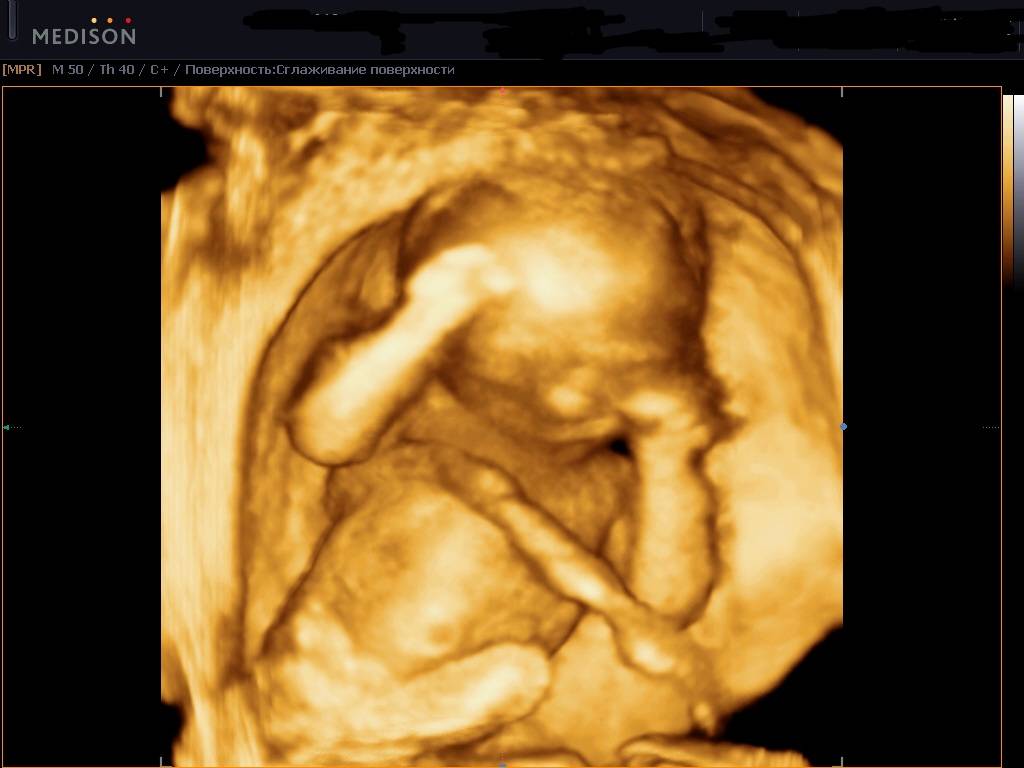

Как вариант, можно пройти 3D-ультразвуковое исследование. Изображение, полученное во время процедуры, выводится на монитор.

Фото:

Малыша на экране можно хорошо рассмотреть, так как изображение объемное. С помощью такого сканирования внимательно изучают все органы малыша, делают замеры, обнаруживают патологии.

Стоит помнить, что подобное исследование можно проводить только во втором и третьем триместрах.